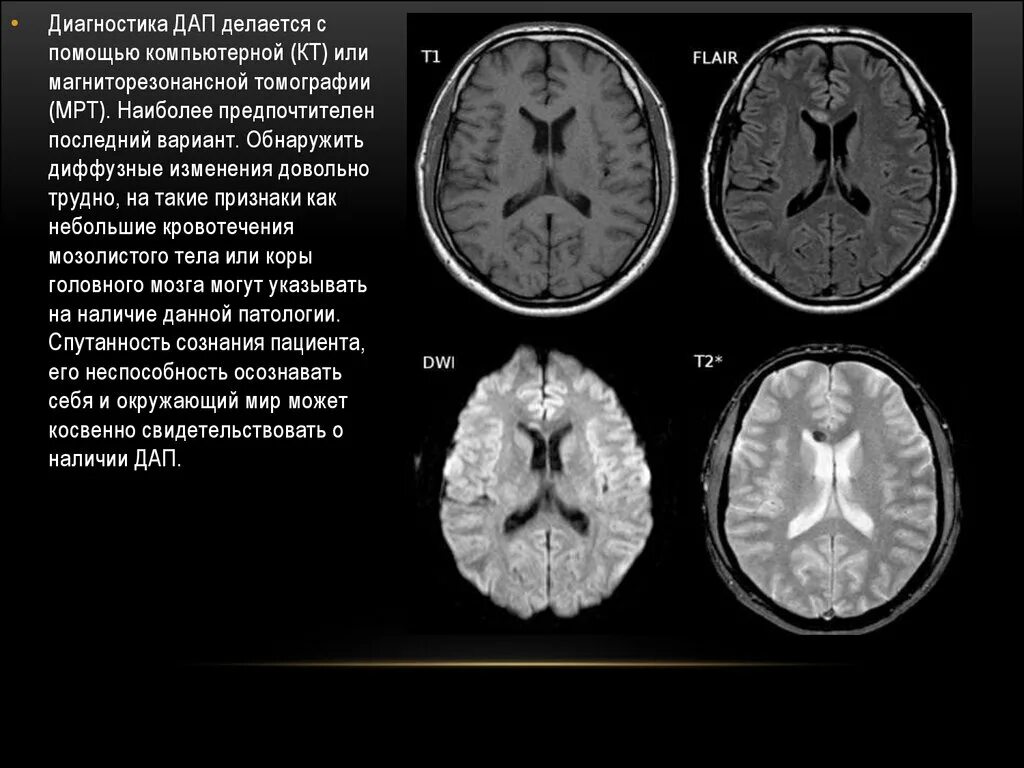

Диффузное аксональное повреждение